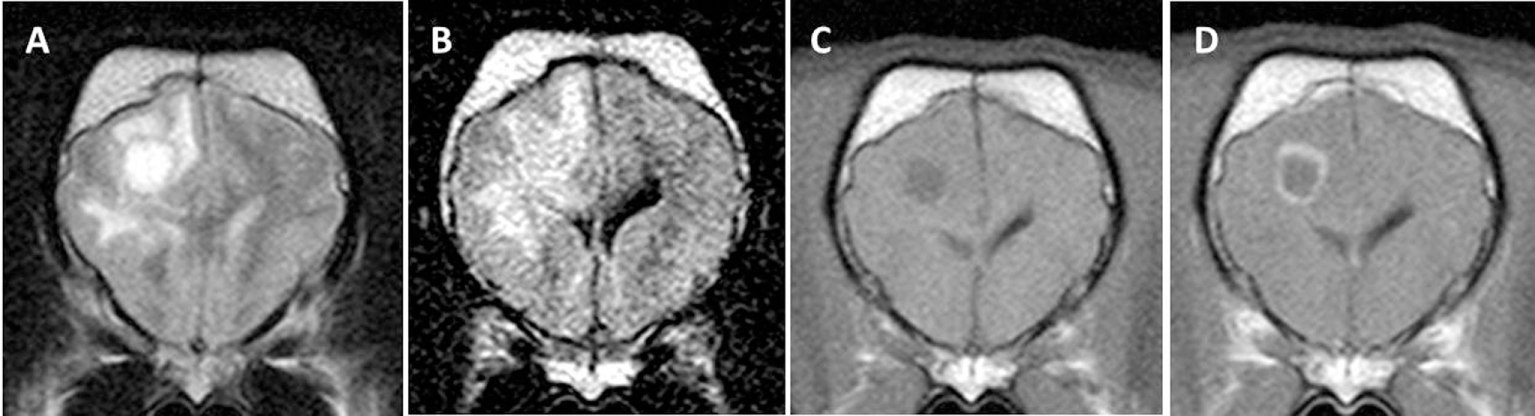

Figure 6. Transverse magnetic resonance images (3 T) of a Chihuahua (11 months, female) with necrotizing meningoencephalitis. T2 (A) and fluid-attenuated inversion recovery (B) hyperintense finger-like lesions affecting the subcortical white and gray matter in the right prosencephalon. These characteristics may resemble those of Yorkshire Terriers with necrotizing leucoencephalitis since there might be a thin rim of intact cortical gray matter. However, involvement of gray matter can be visualized in most cases. The lesion is hypointense on T1-weighted images (C) and is only mildly enhanced in the periphery of the lesion (D).

Figure 7. Transverse magnetic resonance images (3 T) of a Chihuahua (5 years, female) with necrotizing meningoencephalitis. Single T2 (A) and fluid-attenuated inversion recovery (B) hyperintense round-shaped lesion in the right diencephalon. There is a small uniform contrast enhancement in the center of the lesion on the post-contrast T1-weighted image (D) compared to the pre-contrast T1-weighted image (C).